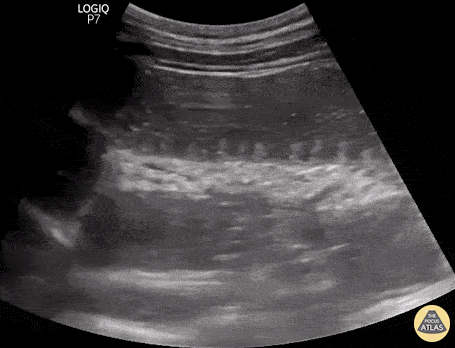

84 yo F presenting with abdominal pain, nausea, vomiting, constipation and abdominal distension for 3-4 days. Bedside ED-performed POCUS show this findings: No compressible and distended small bowel loops (> 2,5 cm), "To-and-Fro" motion of intraluminal content, “valvulae conniventes” on the interior aspect of the bowel wall, which appears like black and white keys of a piano (Keyboard Sign). These ultrasound signs rule-in the diagnosis of Small Bowel Obstruction. Renato Tambelli @JediPocus @R_Tambelli